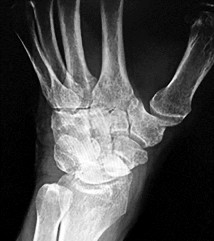

Which of the following describes the correct vascular anatomy and blood supply of the scaphoid, predisposing its proximal pole to avascular necrosis following fracture?

Options:

- The primary blood supply enters at the dorsal ridge and supplies the proximal pole via retrograde flow.

- The primary blood supply enters the proximal pole directly from the anterior interosseous artery.

- The primary blood supply enters the volar tubercle and supplies the bone via antegrade flow.

- The ulnar artery provides the dominant supply to the proximal pole via the deep palmar arch.

- The dorsal carpal branch of the radial artery enters the proximal pole directly.

Correct Answer: The primary blood supply enters at the dorsal ridge and supplies the proximal pole via retrograde flow.

Explanation:

The major blood supply to the scaphoid (70-80%) comes from branches of the radial artery that enter the bone via the dorsal ridge (near the waist) and perfuse the proximal pole in a retrograde fashion. Because of this retrograde flow, fractures at the waist or proximal pole can disrupt the blood supply to the proximal fragment, greatly increasing the risk of avascular necrosis and nonunion.